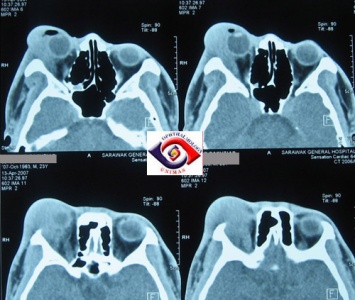

Sclera, episclera, Tenon capsule, and uvea:

Imaging will demonstrate nonspecific thickening of structures. Blurring of the scleral margin may be seen (Figure 5).

Figure 5: CT image showing thickening and blurring of left eye uveoscleral (asterisks). (Courtesy of Z.X. Ding).

Orbital fat

Diffuse infiltration and inflammation will be seen in the orbital fat and may envelop the globe and optic nerve sheath complex (Figure 6).

Figure 6: CT image showing enhancement of orbital fat (asterisks). (Courtesy of Z.X. Ding).